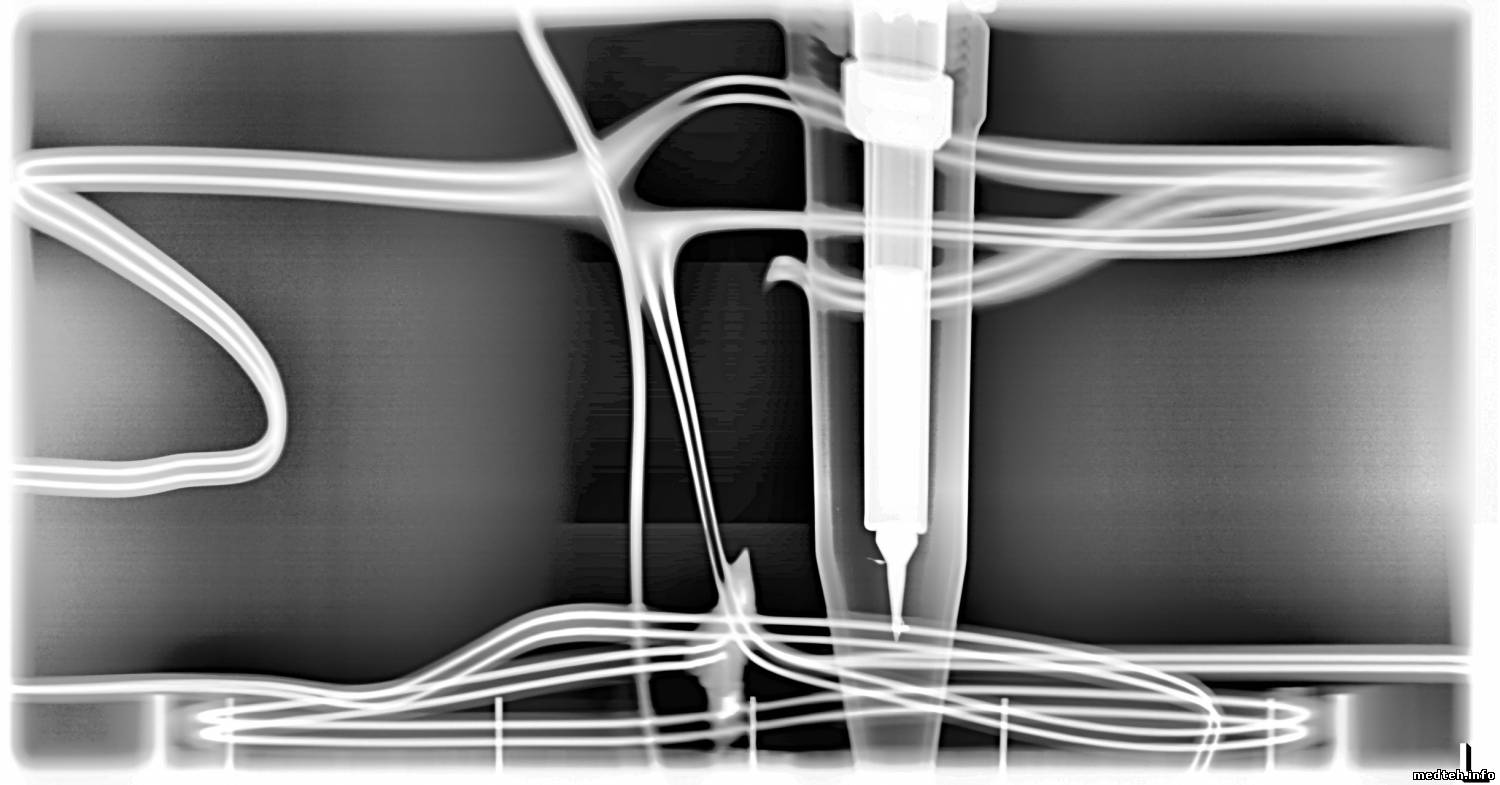

Геометрические искажения, там калибруються тоже программно, а вот горизонтальные полосы на снимке, ума не приложу, как убрать. Несколько снимков во вложении. На середине снимка хорошо видно 3-и приёмника (детектора). Чем дальше,тем хуже. Чётче видны горизонтальные полосы.